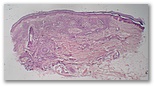

Descripcion histologica

Diagnostico